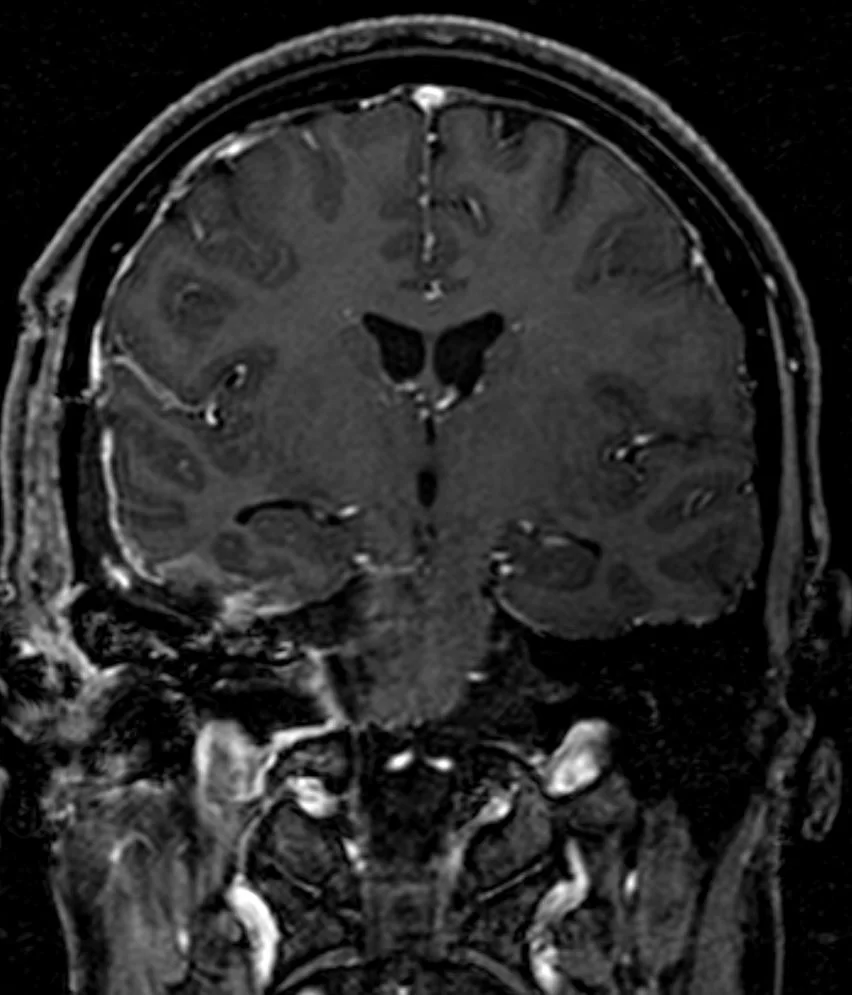

Ο απεικονιστικός έλεγχος με μαγνητική τομογραφία ανέδειξε ευμεγέθη όγκο με επέκταση τόσο στον μέσο όσο και στον οπίσθιο κρανιακό βόθρο και σημαντική πίεση επί του στελέχους, συμβατό με μηνιγγίωμα του λιθοειδούς-αποκλίματος.

Η μετεγχειρητική αξονική τομογραφία εγκεφάλου δείχνει σημαντική μείωση του όγκου, με ελάχιστα υπολειμματικά στοιχεία στην περιοχή του σηραγγώδους κόλπου δεξιά. Η ιστολογική εξέταση ανέδειξε μηνιγγίωμα (WHO I).